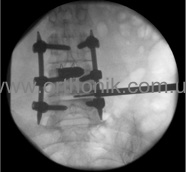

Spondylodesis

This is an operation in which the surgeon connects two (or more) vertebrae, preventing them from further displacement. In some cases, patients suffering from spinal stenosis, together with spondylodesis, are given a decompression laminectomy whose purpose is to fix those parts of the spine in which vertebral displacement or separation has been recorded. Such fixation can help reduce the intensity of pain, improve the patient's performance and general condition.